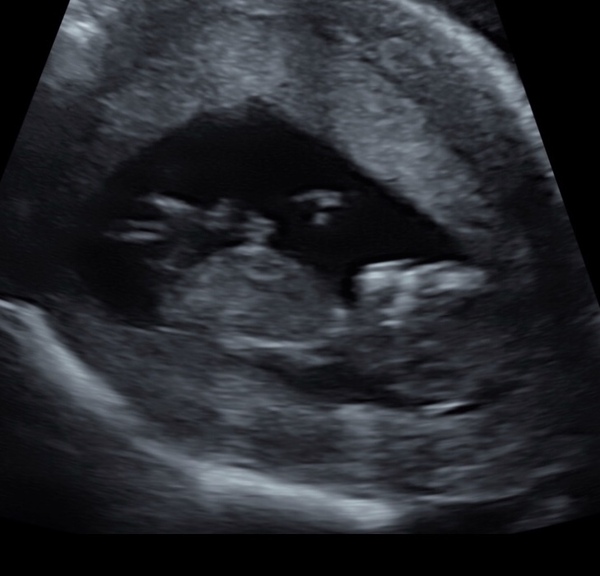

Probably an awful question but had my 12 week scan today (paid for this privately) and going for first ‘official’ dating scan in just under 2 weeks.

Just wondering if anyone thinks baby looks ok from a Down’s syndrome point of view and if anyone can see a nub?

Sorry, picture attached.